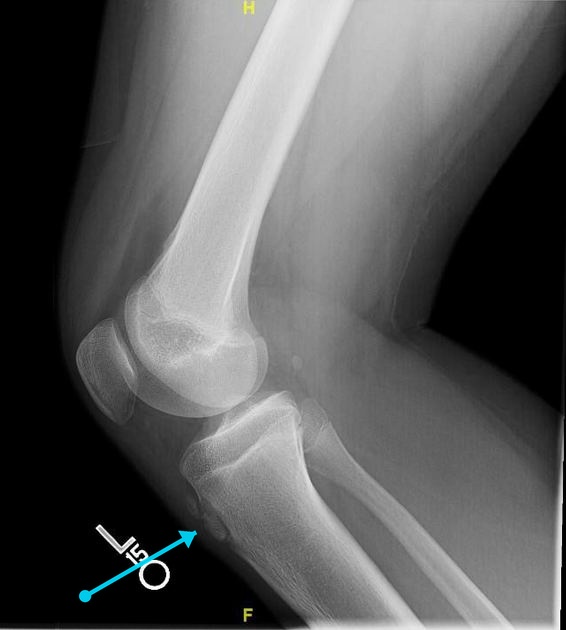

Puzzle 70

Puzzle 70 annotated